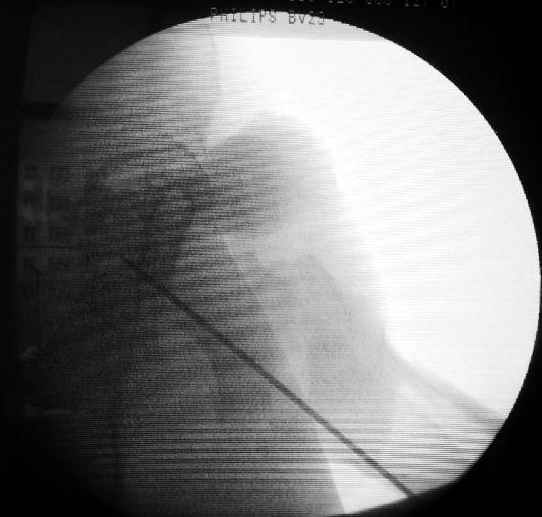

Как раз недавно у меня был примерный случай: больному 36 лет, поступил ночью, травма в результате мотоциклетной аварии, кроме чрезвертельного и спирального перелома левого бедра имеется переломы костей предплечья с этой же стороны. Скелетное вытяжение, а на следующий день больной про оперирован на ортопедическом столе с дистракцией. Чтобы не расколоть чрезвертельный перелом провели временную спицу ближе к переднему кортексу, из малого разреза костодержатель для репозиции, а фиксацию провели антиградным штифтом. Этапы операции на снимках.